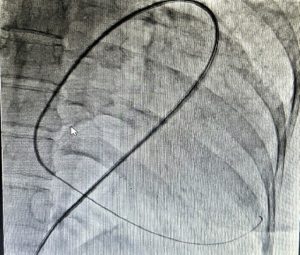

Fluoroscopy was done, and the sheath was found to be in the splenic capsule (Figure 1). Under fluoroscopic guidance, a pigtail was inserted over a 0.035” J-tipped Terumo wire, after confirming the position of the wire in the pericardial space (Figure 2), and 250 ml of pericardial fluid was drained. Post-pericardiocentesis, the patient was vitally stable.